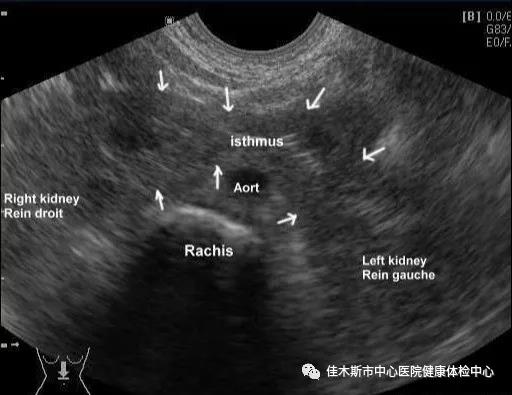

馬蹄腎是指兩側腎的上極或下極在脊柱大血管前相互融合在一起,形成“馬蹄鐵”形的先天性腎臟發育畸形。多發生在胎兒早期(第4~7周),上極融合大多發生較遲,約在第9周,大部分為下極融合,只有少數為上極融合,兩腎融合的部位稱為峽部。

腎臟彩超、CT等影像學檢查顯示兩腎下極或上極相連,橫過下腔靜脈和腹主動脈前方。